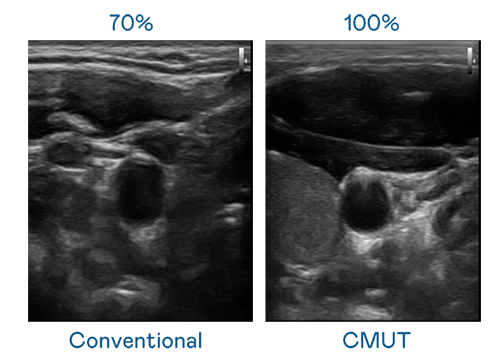

CMUT 技术是一种用电容式微机电元件来产生超音波讯号的技术。与传统 PZT 压电式技术相比,CMUT 频宽增加 30%,更宽频的超音波讯号让影像解析度大幅提升,是实现高影像品质医疗超音波扫描、促进精准医疗发展的关键技术。

大频宽带来超清晰影像

超音波影像的解析度高低,首先取决于探头能发出的讯号频宽。菠菜导航 CMUT 可提供高清晰的超音波讯号,提供高频宽、高灵敏度、影像纹理细节更高的超音波影像,协助医护人员缩短影像判读时间及利用精准的医疗影像进行诊断。